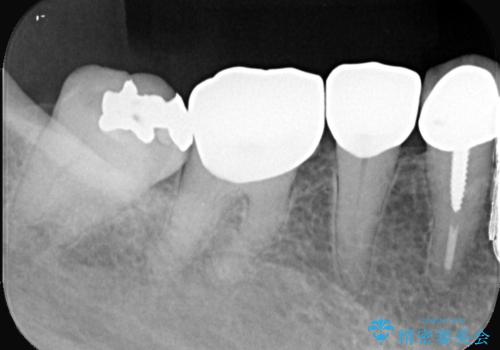

- 主訴:下の歯に詰まっている銀が笑うと見えて嫌だから白くしたい

右下7番目の歯に保険適用のメタルインレーが入っており、大きなう蝕などは認めなかったため概形は大きく変えずセラミックインレーへやり替えとなりました。

やり替える過程で古い裏層材やカリエスは全て除去し、新たにCR裏層を行っています。